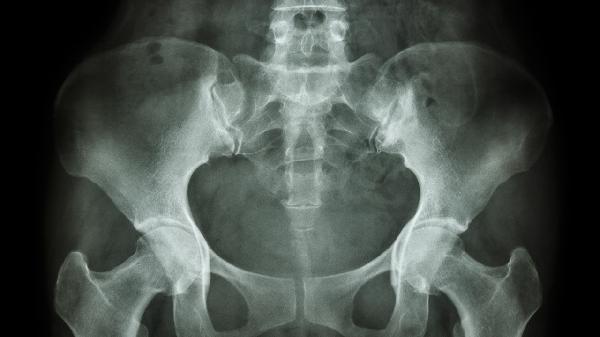

骨盆骨折术后注意事项有哪些 骨盆骨折术后注意四个事项

骨盆骨折术后需注意伤口护理、体位管理、康复训练和定期复查四个事项。骨盆骨折多由高能量外伤导致,术后需严格遵循医嘱以避免并发症。

术后1个月、3个月、6个月需复查X线或CT评估骨折愈合情况。影像学显示骨痂形成且骨折线模糊后方可逐步增加活动量。若出现延迟愈合或不愈合,可能需要二次手术或物理治疗干预。复查时还需监测有无深静脉血栓、异位骨化等并发症。